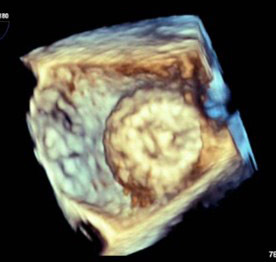

Figure 2. 3D “Top Down” TEE Image of Deployed Watchman Device in Left Atrial Appendage |

![]() |

TEE: transesophageal echocardiography |